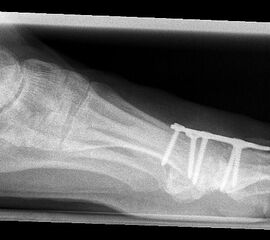

Das nachfolgend präsentierte OP-Verfahren zeigt die Großzehengrundgelenkarthrodese mit Gelenkflächenpräparation mittels sogennanter „Cup-and-Cone“-Fräsen und einer dorsal angebrachten variablen winkelstabilen Platte mit Gleit-/Kompressionsloch.

Durch die Verwendung sogenannter „Cup-and-Cone“-Fräsen und die Osteosynthese mit winkelstabiler Platte ggf. in Kombination mit einer interfragmentären Zugschraube kann die Rate der Pseudarthrosen vor allem bei schlechten Knochenverhältnissen deutlich reduziert werden, sodass dieses Verfahren zunehmend empfohlen wird 9.

Pseudarthrose: Verzögerte Knochenheilung und Pseudarthrosen treten je nach Osteosynthesetechnik unterschiedlich häufig auf. Bei Verwendung von Drähten oder Drahtcerclagen werden hohe Pseudarthroseraten von über 13% beschrieben, daher sollten diese Verfahren verlassen werden1021. Einzelschrauben bieten keine ausreichende Rotationsstabilität und werden daher nur noch selten verwendet. Korrekt eingebrachte gekreuzte Schrauben ergeben zwar bei primärem Hallux rigidus und guter Knochenqulität eine hohe Stabilität, sind jedoch bei osteopenischem Knochen und vor allem bei rheumatoider Arthritis oft unzureichend 141516. Die Rate an Pseudarthrosen kann hier durch Plattenosteosynthese mit interfragmentärer Zugschraube oder mit winkelstabiler Platte mit Gleit-/Kompressionsloch deutlich gesenkt werden 622. Nachteilig ist die Materialstärke der winkelstabilen Platte die zum Teil vermehrt aufträgt und daher gelegentlich die Metallentfernung notwendig macht.